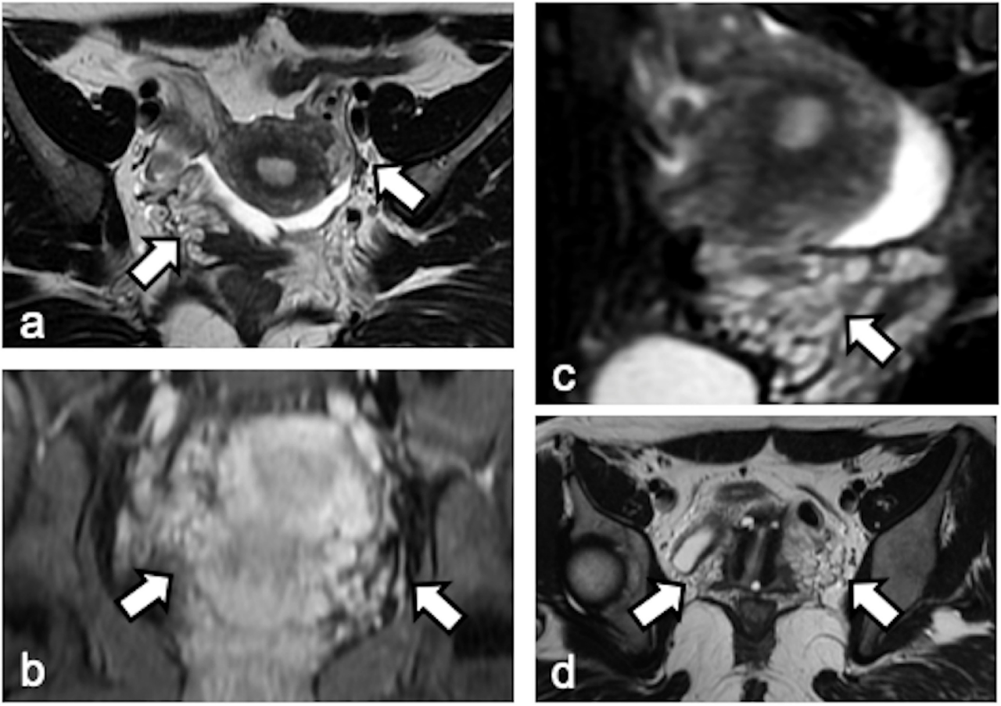

图:PCS磁共振成像:轴位(a)和斜位(d)T2加权图像,T1加权LAVA (b)和T2加权矢状位图像(c)显示盆腔双侧子宫旁静脉淤血扩张(箭头)